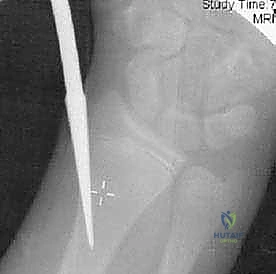

* يتم إدخال سلك معدني رفيع (K-wire) عبر الجلد مباشرة إلى رأس الكعبرة المكسور.

* يُستخدم هذا السلك كـ "عصا تحكم" (Joystick) لتوجيه وتدوير رأس الكعبرة وإعادته إلى مكانه بدقة متناهية.

* بعد الرد، يمكن تثبيت الكسر باستخدام أسلاك تعبر موقع الكسر مؤقتاً، وتُزال بعد التئام العظم.

استخدام سلك معدني (K-wire) كعصا تحكم لتوجيه رأس الكعبرة المكسور بدقة متناهية.

صورة شعاعية تظهر التثبيت النهائي للكسر باستخدام الأسلاك المعدنية المتقاطعة لضمان الاستقرار التام.